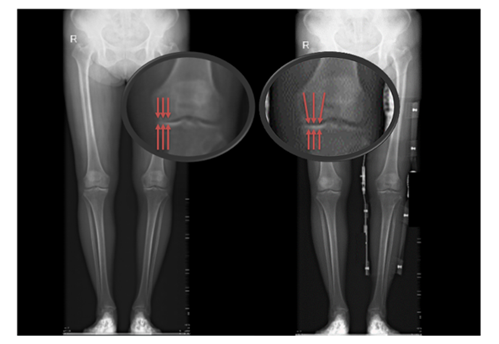

患者未佩戴(左)和佩戴(右)新型矫形支具负重位下肢全长X线片

患者佩戴矫形器行走,并通过步态实验对佩戴支具前后的步态数据进行测算、分析。实验数据结果初步证明,受试者佩戴膝关节内侧减压矫形器后,支撑相后期(膝关节承重的重要周期)膝关节外翻角增大,膝关节内侧力线向外侧转移,膝关节内侧压力降低。对于早、中期的膝骨关节炎患者,佩戴合理设计的膝关节矫形支具能够矫正下肢力线,从而减轻患髁受力,减轻疼痛、改善患处功能并增加膝关节稳定性。

71岁李阿姨,因右膝关节疼痛多年,行走蹒跚,影响生活而来我院骨科就诊,行影像学检查。发现双膝关节间隙狭窄,右膝为主,关节面毛糙,关节面下骨质密度不均,诊断为右膝骨关节炎,行一段时间药物治疗后,疼痛无明显缓解。在九院3D打印门诊佩戴膝关节矫形器,自述目前出行及各项活动都更加方便,活动时已基本不再出现疼痛,对其生活质量明显提高。在佩戴膝关节矫形器后,可旅行、爬山,对于这类运动休闲项目也不再担心出现膝关节的疼痛及不适。